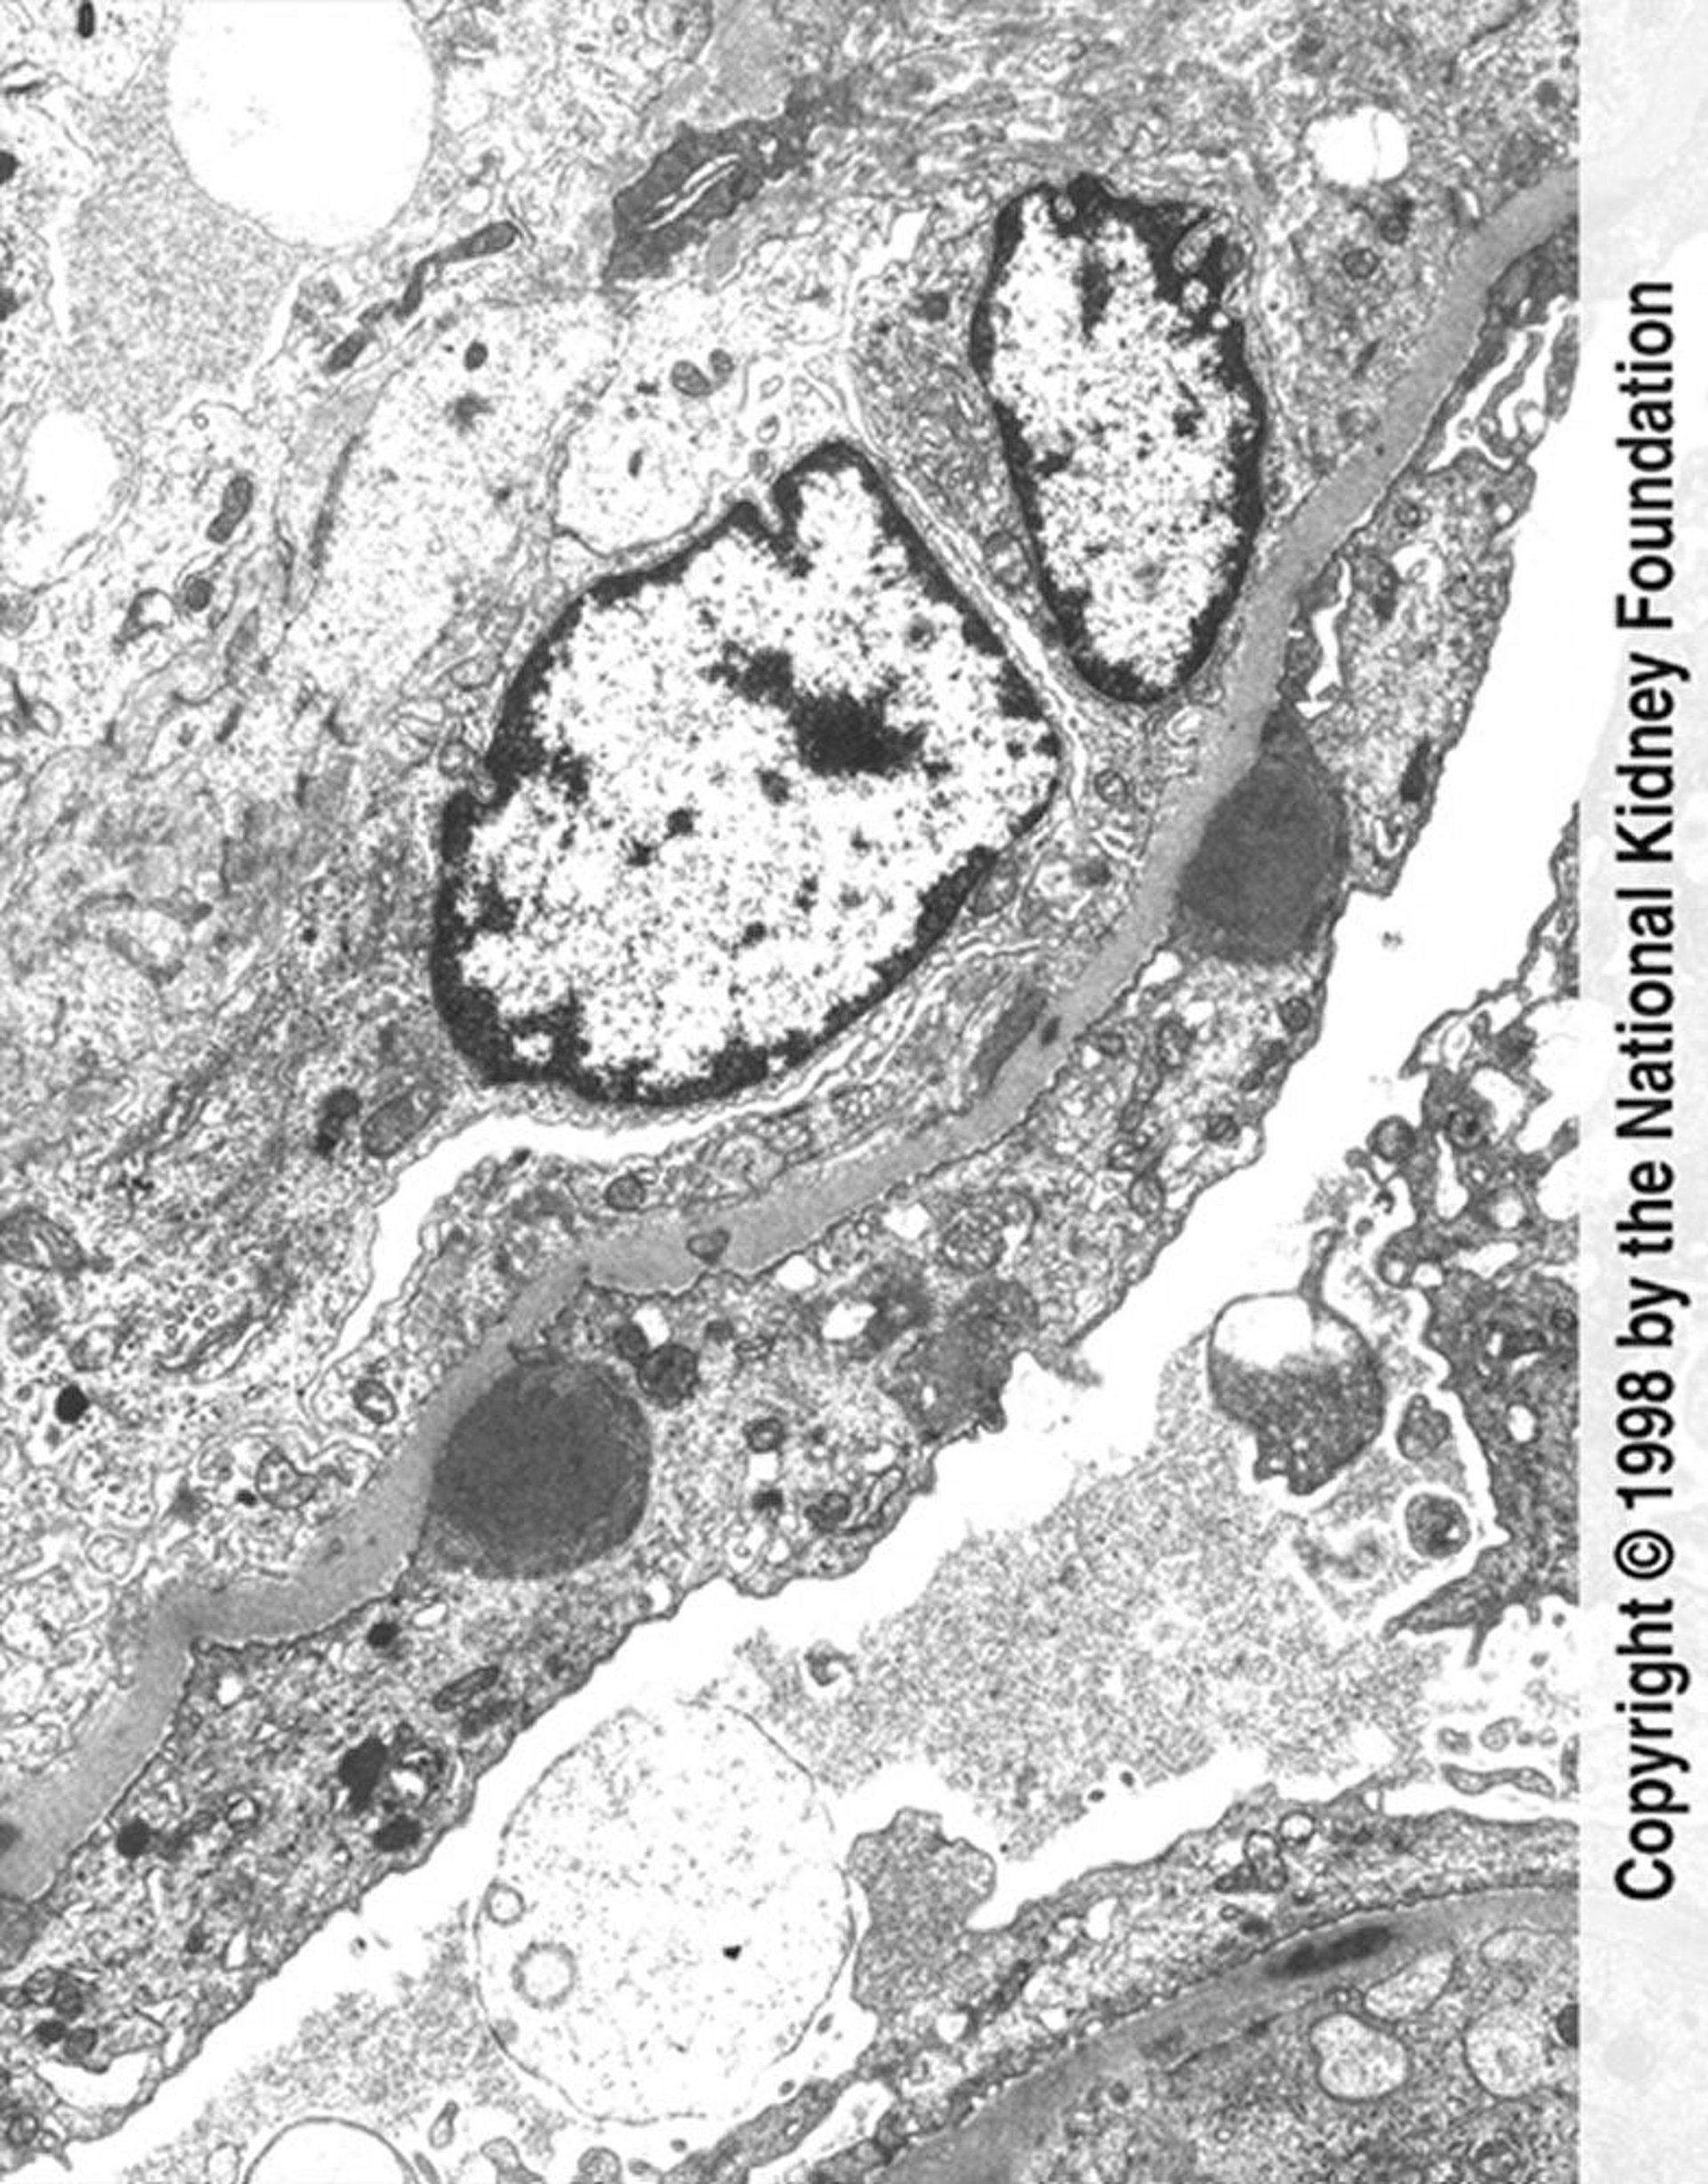

Postinfektiöse Glomerulonephritis (Immunkomplexablagerungen)

Auf der transmissionselektronenmikroskopischen Aufnahme sind buckelförmige Immunkomplexablagerungen (dunkelgrau) mit ausgedehnter Fußfortsatzauslöschung und endokapillärer Proliferation zu sehen (×11.250).

Image provided by Agnes Fogo, MD, and the American Journal of Kidney Diseases' Atlas of Renal Pathology (see www.ajkd.org).